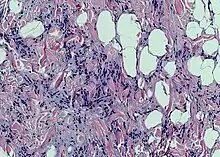

Spindle cell lipoma is an asymptomatic, slow-growing subcutaneous tumor that has a predilection for the posterior back, neck, and shoulders of older men.[1]: 625 [2]